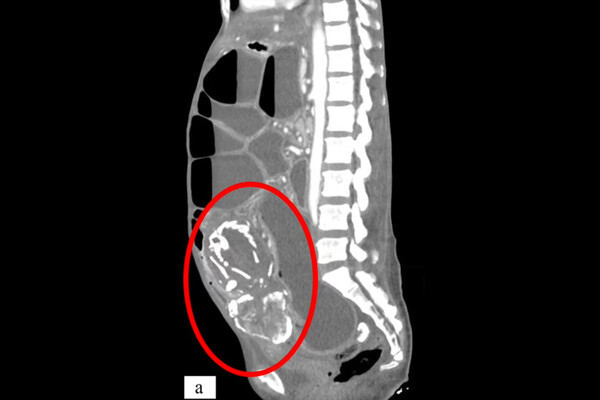

Врачи из Медицинского университета SUNY Upstate рассказали о случае смерти женщины из Конго из-за тяжелого голода, вызванного сдавлением тонкой кишки окаменевшим плодом ребенка, который она носила в своем теле около девяти лет. О случае сообщает Daily Mail.

Женщина родом из Конго обратилась к врачам в Нью-Йорке с жалобами на спазмы желудка. Сканирование обнаружило в теле 50-летней женщины литопедиона —«каменного ребенка», представляющего собой кальцифицированный плод.

Пациентка отказалась от лечения. В конце концов она умерла от недоедания, вызванного плодом, заблокировавшим ее тонкую кишку.

Смерть могла быть вызвана остановкой сердца или аритмией из-за деградации тканей. Также недоедание могло привести к смертельной инфекции.